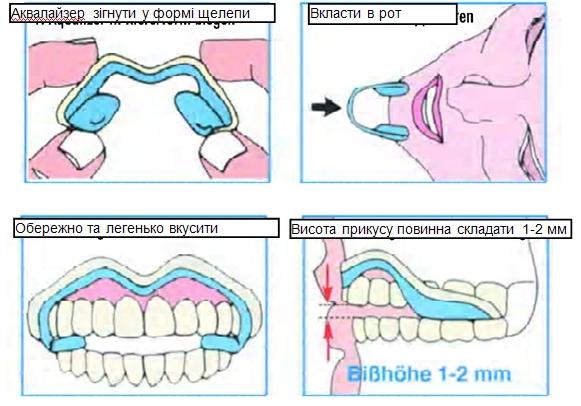

Застосування аквалайзера

Попросіть пацієнта зафіксувати обидві рідинні подушечки своїми премолярами (малими корінними зубами) та корінними зубами. У зв`язку з носінням аквалайзера на короткий час може утворюватися більше слини. Пацієнт при ковтанні слини повинен намагатися максимально розслабити щелепні м`язи і при цьому оперти зуби на аквалайзер. Попросіть пацієнта звернути увагу на значні зміни симптомів (голова, шия, плечі) та повідомляти Вам про них. Цю просту діагностику можна провести також і в приймальні (кімнаті для очікуванна). При цьому потрібно що 10 хв запитувати пацієнта про його симптоми.

Аквалайзер. Використання, реєстрація прикусу